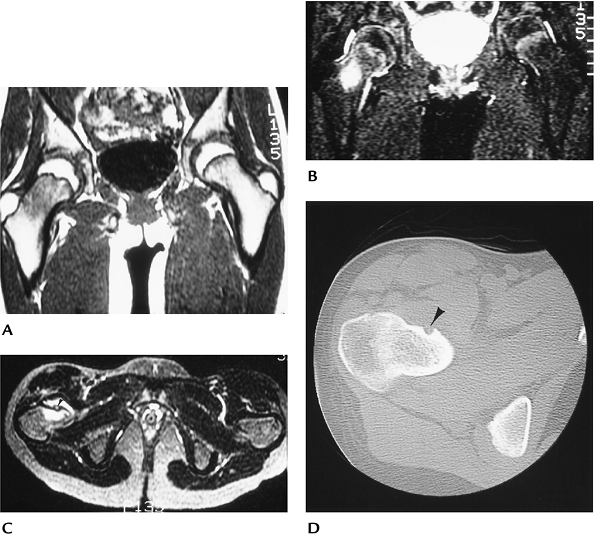

FIGURE 10-10 Osteoblastoma. Sagittal (A) and axial (B)

contrast-enhanced T1-weighted images showing a large enhancing lesion that appears to involve the body and neural arch with spinal cord compression. Axial (C), sagittal (D), and coronal (E) CT images demonstrate matrix calcification or ossification with a thin cortical rim characteristic of osteoblastoma. |